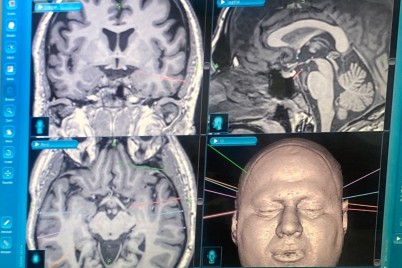

نجح فريق طبي من مركز العلوم العصبية في مستشفى الملك فهد التخصصي بالدمام بإجراء عملية صرع نوعية لمواطن في العقد...